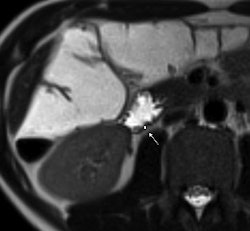

| 1.5-tesla MR images show a portion of the duodenum wall in a patient with untreated celiac disease (above), a patient with treated celiac disease (below), and a healthy patient (bottom). The images show no significant differences in duodenal wall thickness (arrow). |

Their analysis found that a mean maximum enhancement of the duodenal wall was 229.1 ± 46.4 in untreated patients with celiac disease, 109.8 ± 27.8 in treated patients with celiac disease, and 94.7 ± 17.9 in control subjects.

The researchers also found that duodenal wall thickness did not significantly differ between patients with celiac disease who were not treated for the condition, patients with celiac disease who were treated, and healthy control subjects.